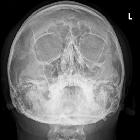

Plain radiograph

Radiographs are not recommended for the assessment of facial trauma due to poor sensitivity for injury.

However, if they are obtained, the diagnosis of fractures involving the inferior or medial wall may be suspected by visualization of fluid with the maxillary sinus and ethmoidal air cells, respectively . A few named signs have been described:

- orbital emphysema may result in a black eyebrow sign

- inferior herniation of the intraorbital fat may result in a "teardrop" sign